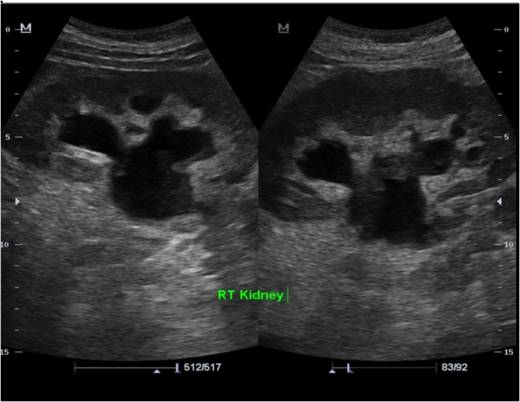

Ультразвуковая диагностика

Ультразвуковые технологии сегодня пользуются огромной популярностью. С их помощью, используя звуковые волны, которые не воспринимаются ухом и имеют частоту выше 20 тысяч герц, можно не только исследовать анатомию почек, но и наблюдать за кровотоком в сосудах этих органов.

Данная процедура абсолютно безопасна, не имеет побочных эффектов и подходит для пациентов всех возрастов, включая детей и беременных женщин.

Ультразвук предоставляет врачу массу полезной информации. Клиническая картина острого и хронического заболеваний значительно отличается.

В случае острого процесса наблюдается увеличение почек и размывание границ между корковым веществом и пирамидами. При этом кровоток в периферических участках значительно снижен. В отличие от этого, при хроническом заболевании размеры почек уменьшаются, а лоханка, наоборот, расширяется. Длительное воспаление может привести к сморщиванию почки и гидронефрозу, при котором лоханка достигает гигантских размеров.

При гидронефрозе на ультразвуковом изображении выделяется большая почечная лоханка темным цветом.